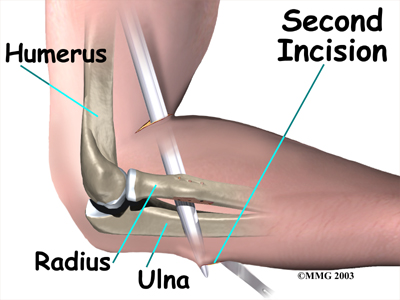

In a direct repair, the surgeon begins by making a small incision across the arm, just above the elbow. Forceps are inserted up into this incision to grasp the free end of the ruptured biceps tendon. The surgeon pulls on the forceps to slide the tendon through the incision.

Attention is given to the . A scalpel is used to slice off the damaged and degenerated end. Sutures are then crisscrossed through the bottom inch of the distal biceps tendon.

A curved instrument is passed through the incision and directly between the radius and ulna bones. The surgeon pushes the instrument through this space, puncturing the muscles and soft tissues. The surgeon feels the back side of the forearm for the spot where the instrument is protruding. A is made at this spot.

The original attachment on the radius, the radial tuberosity, is . An instrument called a burr shaves off the surface of the tuberosity. The burr is then used to create a small cavity in the bone for the tendon to fit inside. Three small holes are drilled into the top of the rim of bone to secure the sutures.

The tendon is passed between the radius and ulna, exiting through the second incision that was made on the back of the forearm. The sutures are threaded into the three holes that were drilled into the rim of the radial tuberosity. The surgeon ties the sutures, securing the . When the surgeon is satisfied with the repair, the skin incisions are closed, and the elbow is placed either in a cast or a range-of-motion brace.